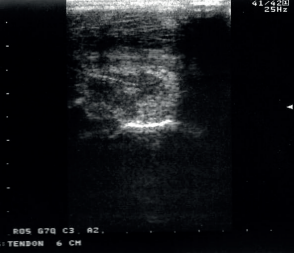

– entre 3 et 10 jours après l’accident

– choix des traitements à réaliser et la convalescence

– donner un pronostic

– aide au suivi et à changer de palier d’activité

– agrandissement naturel de la lésion durant les deux premières semaines

– immobilisation correcte durant les 10 premiers jours permettait de limiter significativement cette augmentation de taille de la lésion (David et al. 2011)